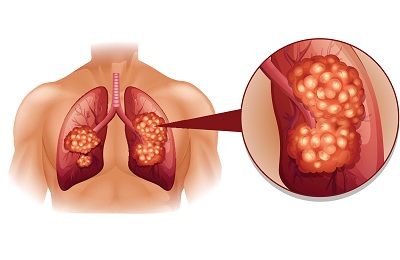

В случае присутствия новообразования злокачественного характера на рентгене будет заметно просветление или затемнение. На начальной стадии, когда диаметр опухоли составляет менее 5 мм, заболевание может быть незаметно при таком методе диагностирования.

Сложность определения ракового процесса в легких на первой стадии с помощью рентгеновского снимка заключается в том, что маленькие опухоли могут попросту никак себя не проявлять.

Теперь рассмотрим, как выглядит рак легких на снимке рентгена, если речь идет о его центральном расположении. Опухоль проявится таким образом:

- Появление темного участка (инфильтрация).

- Нарушенная вентиляция.

- Соседним отделам свойственна компенсационная воздушность. Она возникает по той причине, что при сильном поражении участка легкого органу требуется компенсация для нормализации процесса снабжения кислородом окружающей ткани.

Если у больного присутствует центральный рак главного бронха, то опухоль имеет типичные симптомы, а потому опытный рентгенолог без труда распознает начало развития патологии. Центральный рак на рентгеновском снимке проявляется как тень, имеющая негомогенную структуру с бугристым контуром. С одной из сторон такая тень нередко оказывается покрытой язвами.

В том случае, если опухоль сдавливает другие органы, то в плевральной полости может появляться жидкость.

Если новообразование развилось в верхней части легкого, то его нередко принимают за туберкулезный инфильтрат. Однако если речь действительно идет о раке, то на рентгене явно заметны очаги разрушения. Затемнение, создаваемое опухолью, характеризуется неровным фестончатым контуром.